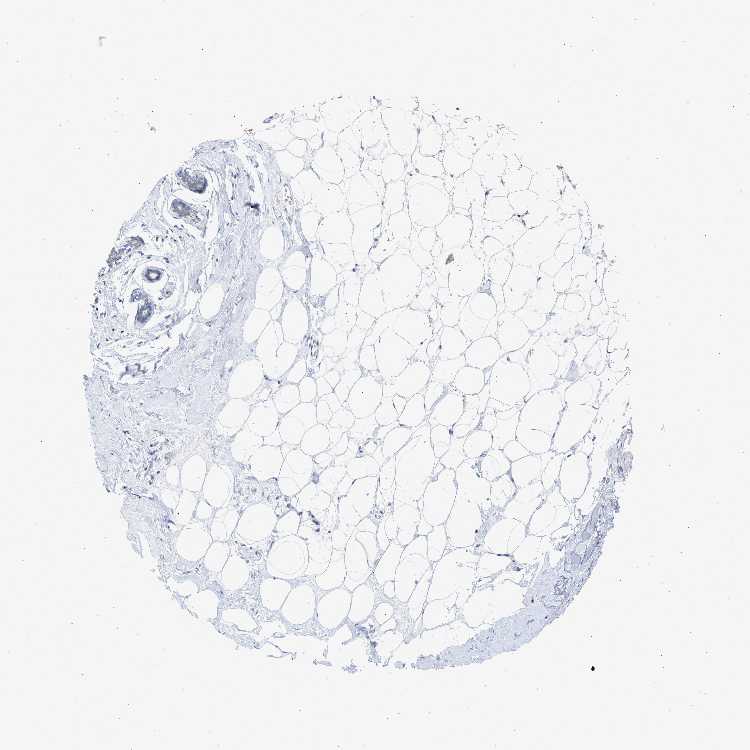

TISSUE PRIMARY DATA SOFT TISSUE Show tissue menu

SOFT TISSUE - Expression summary

SOFT TISSUE 1 - Antibody stainingi

Antibody staining in the annotated cell types in the current human tissue is reported as not detected, low, medium, or high, based on conventional immunohistochemistry profiling in selected tissues. This score is based on the combination of the staining intensity and fraction of stained cells.

Each image is clickable and will lead to virtual microscopy that enables deeper exploration of all samples and also displays staining intensity scores, fraction scores and subcellular localization as well as patient and tissue information for each sample.

Antibody HPA019881Antibody HPA057134

Chondrocytes -High

Fibroblasts Not detectedNot detected

Peripheral nerve Not detectedNot detected